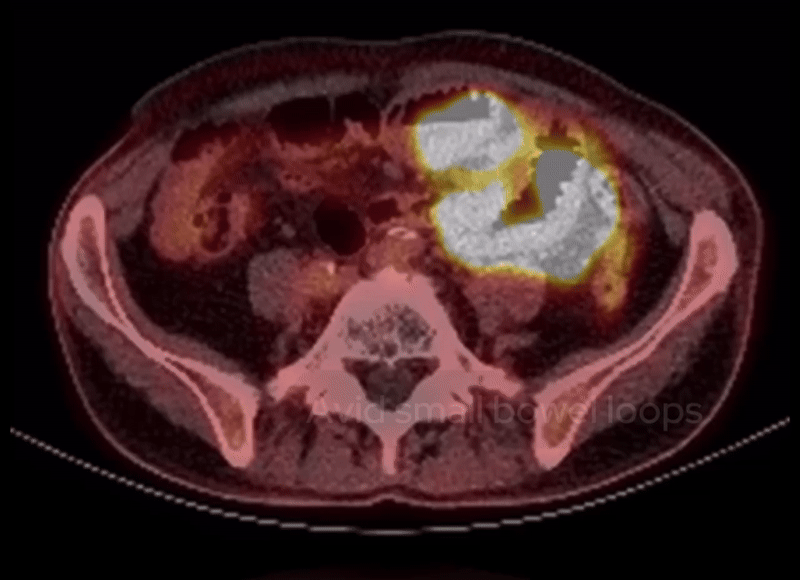

A PET-CT scan was performed to further evaluate the extent of disease. Let’s go through the findings:

• Gastric mass: Intense FDG avidity confirms active disease.

• Retroperitoneal node: Left para-aortic lymph node shows avid uptake.

• Small bowel: FDG uptake throughout the segment of mural thickening.

These findings reinforce the diagnosis of lymphoma. An upper gastrointestinal endoscopy (OGD) with a biopsy confirmed the diagnosis of lymphoma.

PET-CT shows FDG avidity within the gastric lesion, small bowel loops as well as a left para-aortic lymph node.